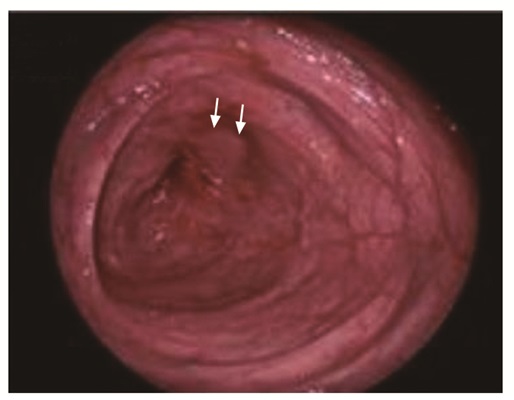

• 摘要: 肠腔狭窄是常见的克罗恩病(Crohn's disease,CD)并发症,15%的CD患者在首诊10年内可发展为肠腔狭窄。CD并发肠腔狭窄根据病理类型可分为炎症型、纤维型及混合型,炎症型为主的患者可通过药物治疗缓解症状,而纤维型为主的患者则只能通过介入或手术治疗,故采用影像学手段全面评估狭窄肠段的数目、部位、形态,并区分肠壁炎症和纤维化程度,对于临床决策十分重要。近年来,多项影像学新技术在鉴别狭窄肠壁炎症及纤维化方面取得了较大进展,有望在临床推广应用,进一步提高CD并发肠腔狭窄的诊疗。本文综述主要影像学手段包括内镜、CT、MRI、经腹超声等对肠腔狭窄的诊断价值,以期为临床提供参考。

Abstract: Intestinal stricture is one of the most common complications of Crohn's disease(CD). About 15% of CD patients can develop intestinal stricture within the first 10 years after diagnosis. CD complicated with intestinal stricture can be divided into inflammatory, fibrous and mixed types according to pathological changes. Patients with the inflammatory type can alleviate symptoms by drug treatment. In patients with the fibrous type, the affected intestinal segments can only be treated by interventional or surgical treatment. Therefore, it is very important for clinical decision-making to comprehensively evaluate the number, location and shape of narrow intestinal segments, and to distinguish the degree of inflammation and fibrosis of the intestinal wall. This article reviews the sensitivity and specificity of the main imaging methods including endoscopy, CT, MRI, and trans-abdominal ultrasound in the diagnosis of intestinal stricture. In recent years, many new imaging techniques have made great progress in differentiating inflammation and fibrosis of the narrow intestinal wall, which is expected to be widely used in clinical practice and to further improve the diagnosis and treatment of CD complicated with intestinal stricture.